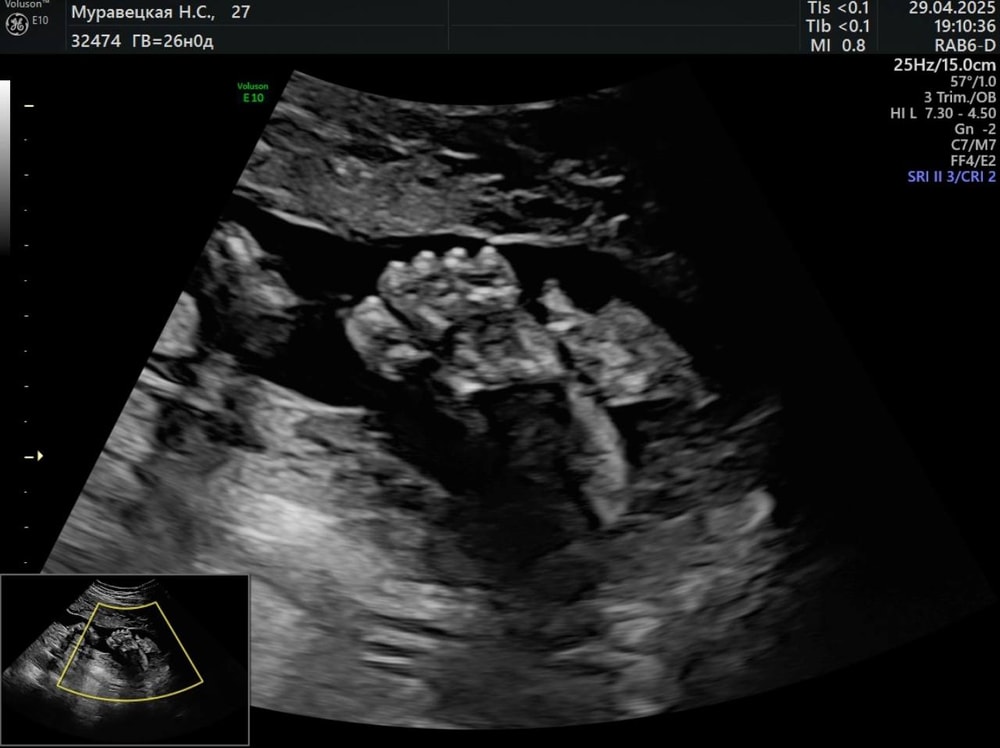

УЗИ

Была вчера у Сергея Александровича Тё. По УЗИ малыш опережает аж на 5 дней свой срок, весит 999 гр и длиной 34 см. На узи лежал не очень удобно, поэтому мы почти час делали исследование, крутились, вертелись, в итоге поймали личико 😊😍В прошлую пятницу прошла "всеми любимый" глюкозотолерантный тест. Мне так было жалко платить за него деньги (в ЖК дали направление аж в 30 недель почти, нас не будет в Москве), поэтому я пошла по ДМС к эндокринологу, чтобы мне дали направление на ГТТ, меня решили обследовать по-полной, поэтому я сдала еще биохимию с полным исследованием по железу, ОАК, ОАМ, ТТГ,Т4, гликированный гемоглобин. Все анализы в норме и даже ферритин 32!!!, я была в шоке, девочки, тк я пью пока по 1 таб сорбифера всего лишь, мне казалось к 3 триместру он рухнет до 0.